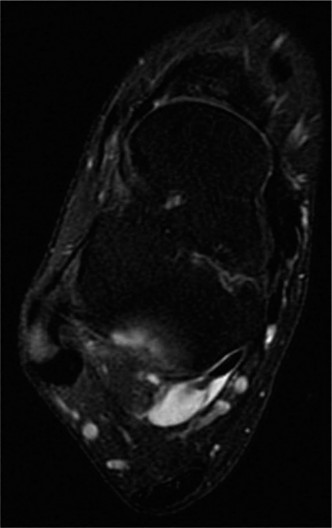

A 52-year-old male presents to your office reporting increased medial and lateral hindfoot pain for the past …